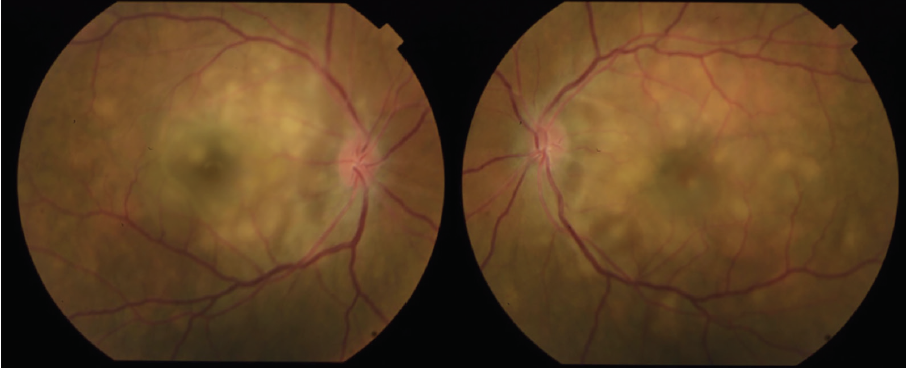

Dilated fundus examination revealed clear media without inflammation OU and numerous deep, discrete, and patchy yellow lesions throughout the posterior pole with irregular borders and multiple areas of distinct retinal elevation OU (Figure 1). The optic nerves were noted to be hyperemic OU without significant elevation, hemorrhage, or obscuration of vessels. Of note, there was no evidence of peripheral pathology or retinal vasculitis. OCT imaging showed numerous areas of intraretinal and subretinal fluid pockets of varying size with notable retinal and choroidal undulation through the macula (Figure 2). Fluorescein angiography showed multiple irregular patchy and pinpoint areas of hyperfluorescent foci throughout the posterior pole with leakage and distinct pockets of pooling in the later frames (Figure 3).

Figure 1. Color fundus photography on presentation shows numerous subretinal discrete yellow lesions throughout the posterior pole with irregular borders and multiple areas of distinct retinal elevation OU.